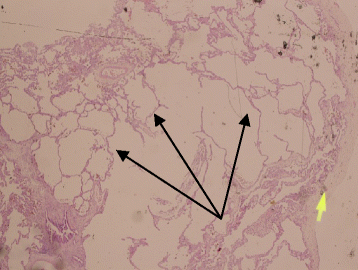

Background: Mutations in the gene encoding filamin A (FLNA) lead to diseases with high phenotypic diversity including periventricular nodular heterotopia, skeletal dysplasia, otopalatodigital spectrum disorders, cardiovascular abnormalities, and coagulopathy. FLNA mutations were recently found to be associated with lung disease. In this study, we report a novel FLNA gene associated with significant lung disease and unique angiogenesis.

Case presentation: Here, we describe a 1-year-old Saudi female child with respiratory distress at birth. The child then had recurrent lower respiratory tract infections, bilateral lung emphysema with basal atelectasis, bronchospasm, pulmonary artery hypertension, and oxygen and mechanical ventilation dependency. Molecular testing showed a new pathogenic variant of one copy of c.3153dupC in exon 21 in the FLNA gene.